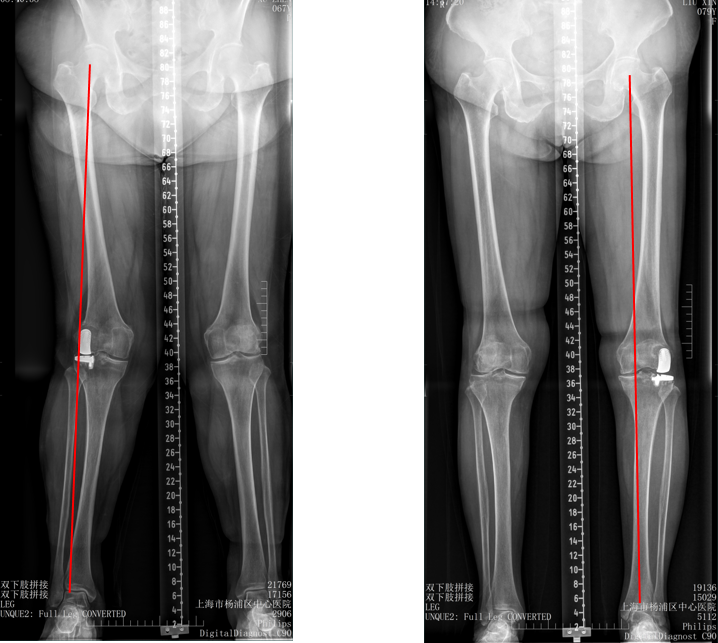

五、一期双单髁置换LINK:registered: SLED假体位置

双间室OA行Bi-UKA

正位片标准胫骨和股骨假体位置

AP位假体位置:内侧和外侧单髁分别按照各自的手术原则独立开展,假体的位置也按照各自的标准进行考量,需要综合考量的是胫股角,关节线,中央髁间隆突。

侧位片标准胫骨和股骨假体位置

侧位假体位置:内侧和外侧单髁分别按照各自的手术原则独立开展,假体的位置也按照各自的标准进行考量。

双间室OA行Bi-UKA术后内侧假体周围骨折ORIF

六、二期双单髁置换LINK:registered: SLED假体位置

1、内侧UKA术后外侧间室进展性OA

2、外侧UKA术后内侧间室进展性OA

3、内侧UKA术后外侧进展OA行Bi-UKA术后内侧垫片脱位

MUKA外侧OA进展行Bi-UKA术后内侧Bearing脱位翻修